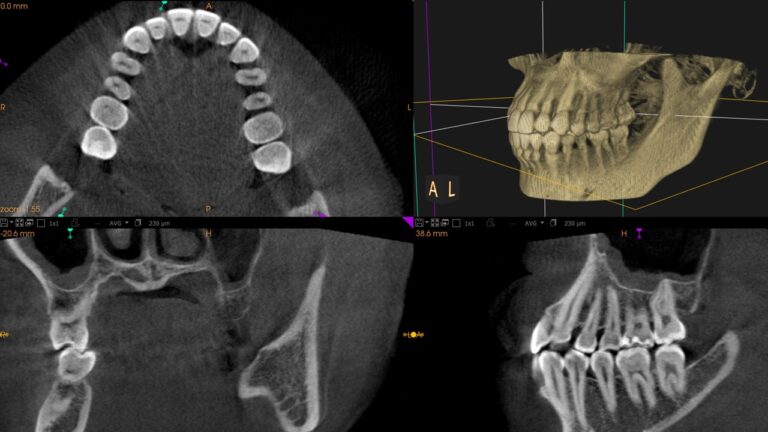

歯科用CT(X-ERA MF)

一般医科用のCTよりも被曝量が少ない機器を導入しています。CTはレントゲンとは異なり、3次元的に歯や顎の状態を把握できるのでより精度の高い診断を行うことができます。